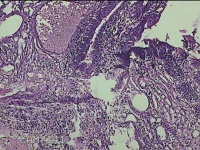

3、7、11点肿物

性别

男

年龄

34岁

临床诊断

1.混合痔 2.肛裂

一般病史

大便出血半年,伴粘液便。

标本名称

大体所见

灰白暗红色肿物1.8x1x0.3cm两个,表面糜烂。

图2

痔是有的。